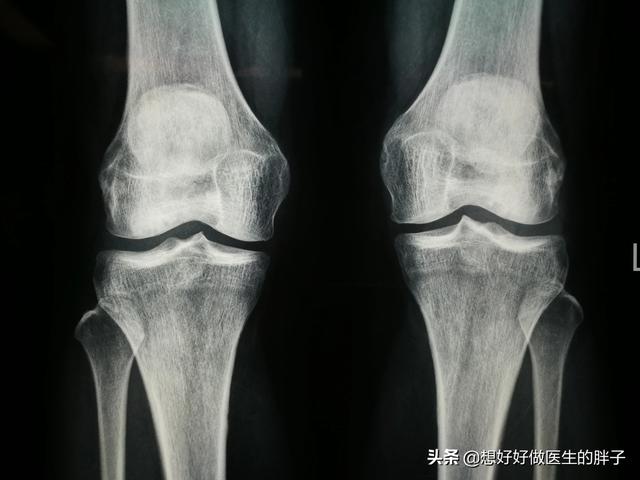

Si le patient souffre de douleurs articulaires dues à l'arthrose, il est recommandé de procéder à des examens appropriés à l'hôpital.Radiographie du genouLes radiographies nous permettent de déterminer si le patient souffre d'une graveformation d'os grasEst-ce que leSténose de l'espace articulaireIl s'agit d'une évaluation préliminaire de l'état du genou.

Le médecin déterminera généralement le stade de la maladie auquel se trouve le patient sur la base de radiographies et d'une IRM du genou.

Les radiographies confirment la présence d'un rétrécissement de l'espace articulaire, d'une surcharge des articulations et d'une sclérose des surfaces articulaires de l'ensemble de l'articulation du genou.